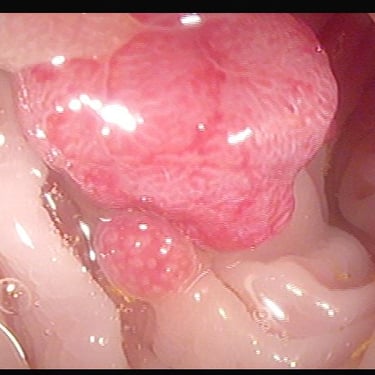

Tumores gástricos

Pólipo de colon

Resección de polipos del colon

(polipectomía)